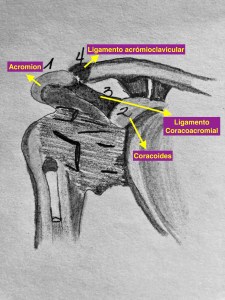

En el corte axial de las imágenes 3 y 4 puedes ver la anatomía radiológica implicada. La relación es perfecta, y completamente explicativa de la situación resulta mediante el tratamiento quirúrgico. En ella la Arteria iliaca derecha para justo por encima de la Vena iliaca Izquierda con la capacidad de poder comprimirla.